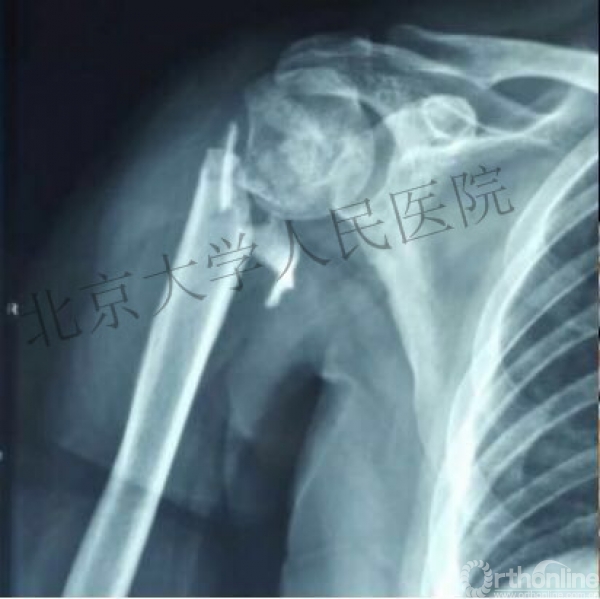

内侧皮质粉碎,低位外科颈骨折,肱骨头-干角维持困难。

术后复位丢失,肱骨头内翻畸形。

能否该偏心固定(钢板)为髓内固定,增加力臂?

此时对比髓内钉是不是有很大优势?